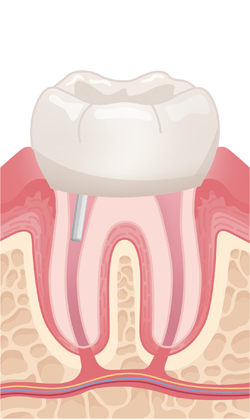

When a tooth is severely damaged or decayed, an infection can form and spread to the nerve tissue and pulp. To repair and save the tooth, a root canal treatment is performed by our endodontist. During the root canal procedure, the infected nerve and pulp are removed and the inside of the tooth is cleaned and sealed.

A tooth that has had a root canal treatment is not as sturdy as before, due to the removal of a large portion of the pulp. Thus it is common that the root canal treatment is followed by restorative procedures to place a post, core and crown.

A post is inserted to support the tooth. The opening is sealed with a filling.

The treated tooth is sealed with new crown.